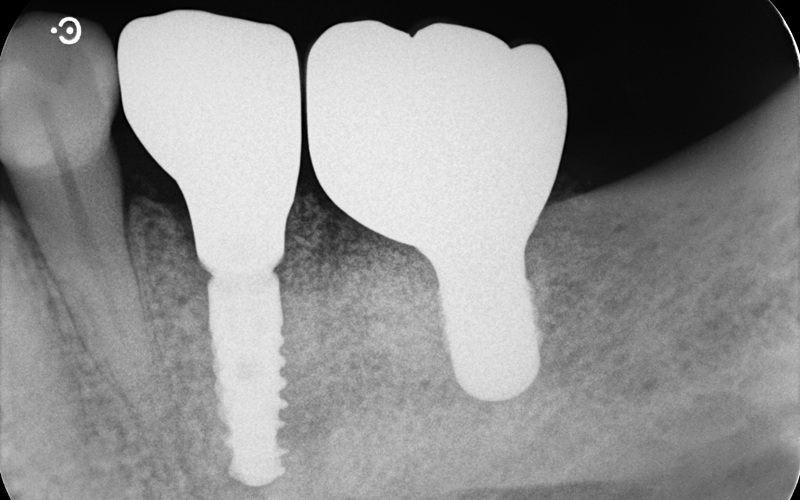

Case4

| 治療名 | GBRとインプラントを行った症例 |

| 治療説明 | インプラントを埋入予定の部位において、骨の吸収が見られたため、インプラント埋入と同時に小規模な骨造成(GBR)を行いました。治癒期間を経て、最終的にセラミックの上部構造を装着し、自然な見た目としっかりとした噛み合わせを回復しました。 |

| 治療回数・期間 | 6ヶ月 |

| 副作用とリスク | インプラント治療は、入れ歯やブリッジに比べて治療期間が長くなる傾向があります。骨造成が必要な場合は、さらに治療期間が延びることがあります。 また、手術後には一時的な違和感や痛み、腫れ、出血などが生じる場合がありますが、通常は2日〜1週間ほどで落ち着きます。 |

| 料金(税込) | GBR〈小規模骨造成〉:110,000円 インプラント一次手術:220,000円 二次手術:55,000円 上部構造〈セラミック〉:165,000円 合計:550,000円 |